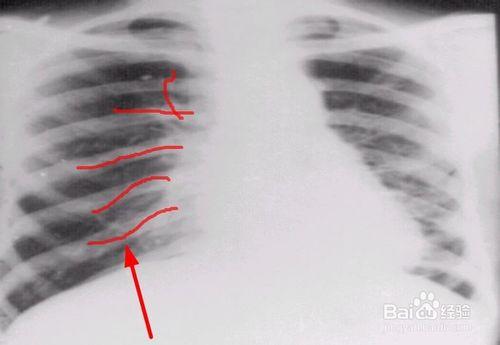

支气管扩张x线表现

支气管扩张胸片

支气管扩张x光